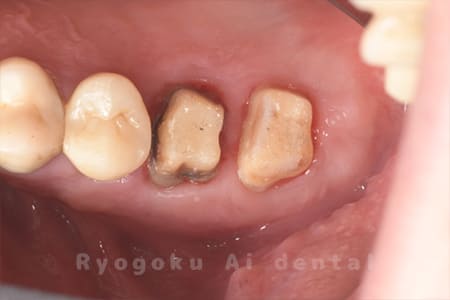

Case14

-

- 原因

- 重度カリエス

- 治療内容

- クラウンレングスニング

- 治療費用

- 44,000円(別途被せ物の費用あり)

被せ物が何度も外れてしまう、とのことでご来院された患者様です。埋まっている部分の歯をクラウンレングスニング手術で十分に出しました。今後型取りを行い、被せ物を行います。